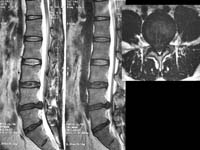

¾çÃø

»óÁö ÅëÁõÀ» ÁÖ¼Ò·Î ³»¿øÇÑ È¯ÀÚÀÇ °æÃߺÎ

MRI¼Ò°ß, ¼ö¼úÈÄ ¼Ò°ß

<Ç㸮µð½ºÅ©>

<¼ö¼úÀü>

<¼ö¼úÈÄ>

Á¦

4.5¹ø ¿äÃߺΠÃß°£ÆÇ Å»ÃâÁõÀ¸·Î ¼ö¼úÇÑ

ȯÀÚÀÇ ¿äÃß MRI¼Ò°ßÀ¸·Î ¼ö¼úÈÄ Å»Ãâ

µð½ºÅ©ÀÇ Á¦°ÅµÈ ¸ð½À°ú ÀûÃâµÈ µð½ºÅ©¸¦

º¼ ¼ö ÀÖ´Ù.

<ôÃß°ÇùÂøÁõ>

ÇÏÁö ¹æ»çÅë°ú °£ÇæÀû ÆÄÇàÀ» ÁÖ¼Ò·Î ³»¿øÇÑ

ȯÀÚÀÇ ¿äÃߺΠMRI ¼Ò°ßÀ¸·Î ôÃß°ü ÇùÂøÀ¸·Î

ÀÎÇØ ô¼ö½Å°æÀÌ ¾Ð¹Ú ¹Þ´Â ¼Ò°ßÀ» º¼

¼ö ÀÖ´Ù.